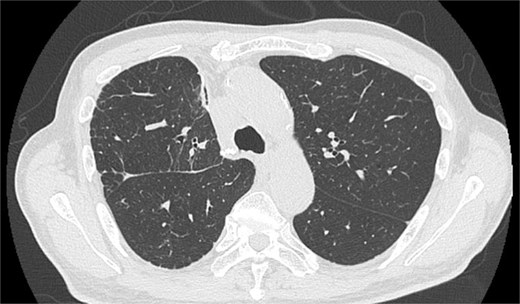

On POD 6, SE developed and spread to the chest, neck, and face. CT demonstrated remarkable mediastinal and SE with minimal lung collapse (Fig. 2; Video 2). Therefore, a chest tube was inserted, but minimal AL occurred from the chest tube, and the emphysema worsened. On POD 11, we performed thoracoscopic exploration and therapeutic intervention. Dense adhesion was confirmed between the staples on the interlobular plane and the dissected upper mediastinum. These were released, revealing the previous pleural tear. No other causative factors were observed. CT and operative findings suggested late-onset AL into the dissected mediastinum through dense adhesions. A leak test under positive pressure of up to 20 cmH2O revealed no AL from the pleural tear. The tear was sealed using a PGA sheet and fibrin glue, and 130 ml of autologous blood was injected into the pleural space to seal the dissected mediastinum and prevent air inflow (Video 3).

Image of postoperative mediastinal and SE with little lung collapse.